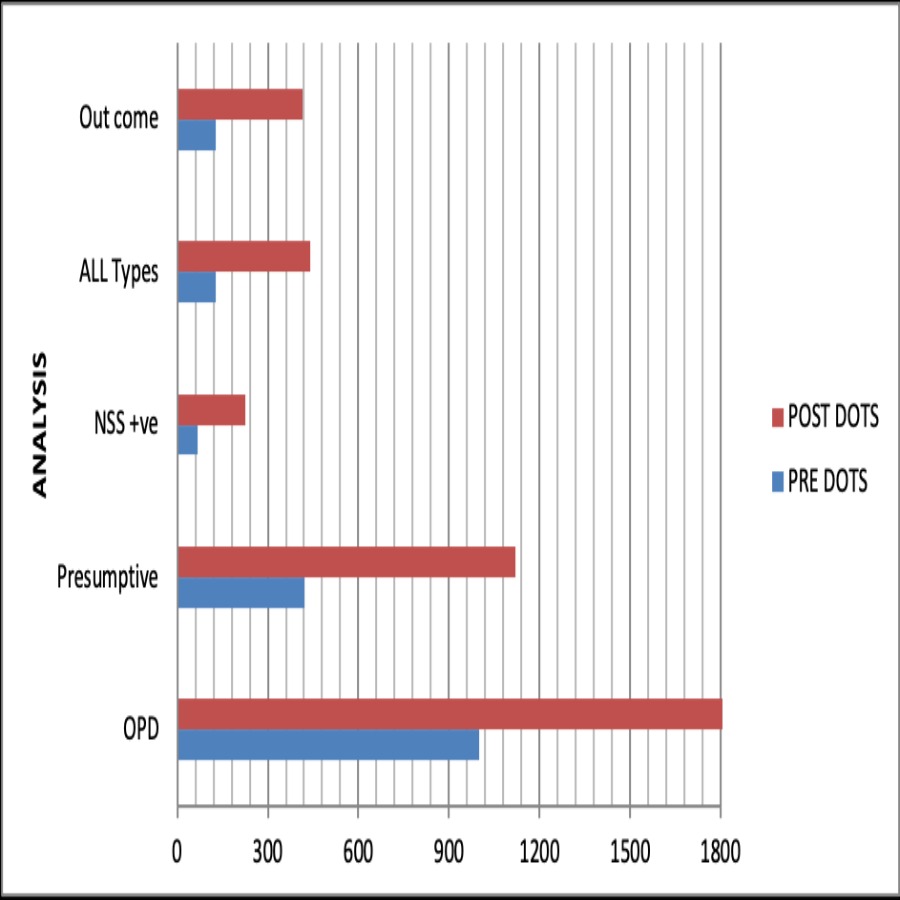

Health